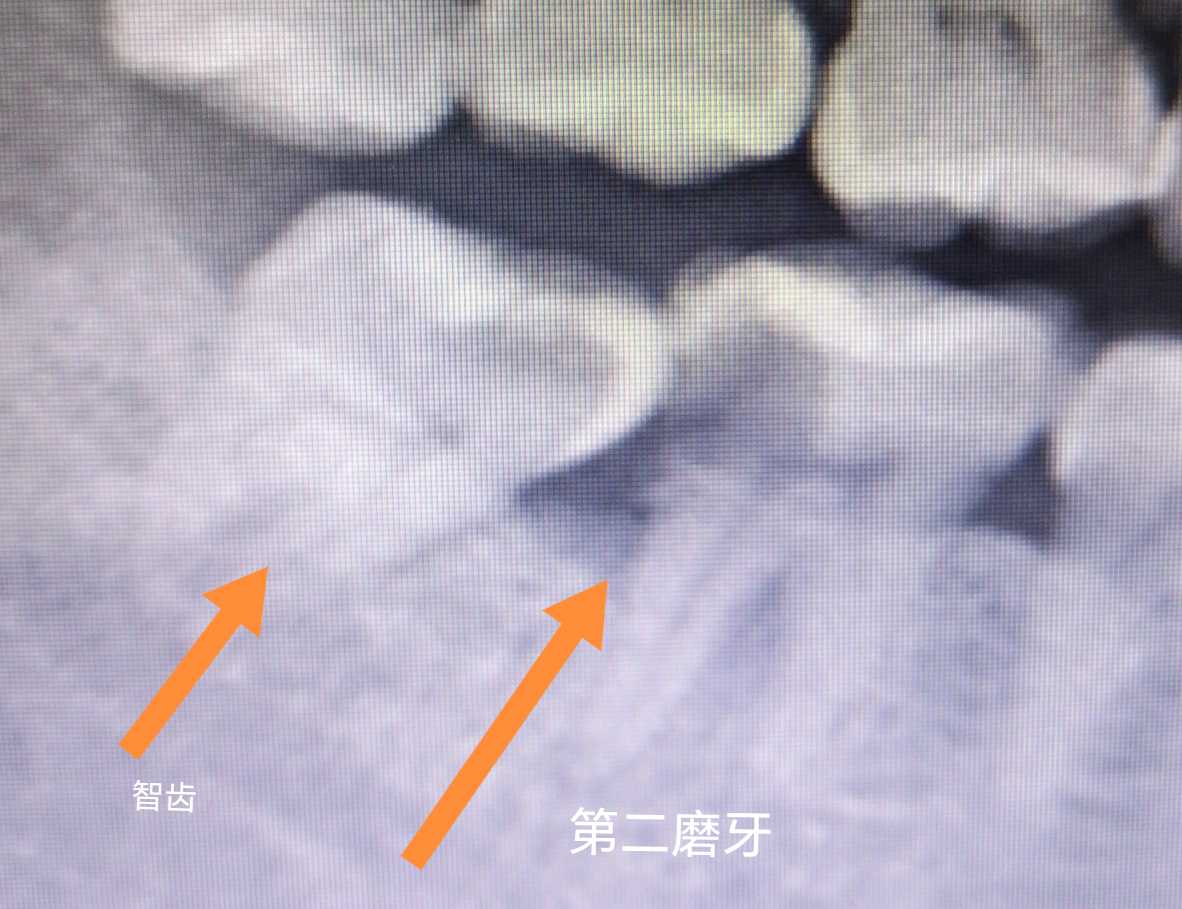

图1和图2是另一个病例,也是智齿导致了下颌第二磨牙牙髓炎。患者一年多前已经发现了下颌第二磨牙远中邻面龋坏,没有及时拔除智齿和治疗下颌第二磨牙。一年多后下颌第二磨牙已经发展为牙髓炎。现在已经拔除了智齿,下颌第二磨牙做了根管治疗,后续还需要冠修复。患者如果去年就选择拔除智齿的话,下颌第二磨牙只需要补牙就可以了。如果患者年轻时就选择拔除阻生智齿的话,下颌第二磨牙远中就不会发生食物嵌塞,也不会蛀牙了。